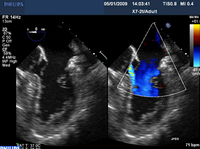

Regurgitação mitral

Prolapso do folheto P2 da valva mitral: visualização 2D

Do acervo de Prakash P. Punjabi